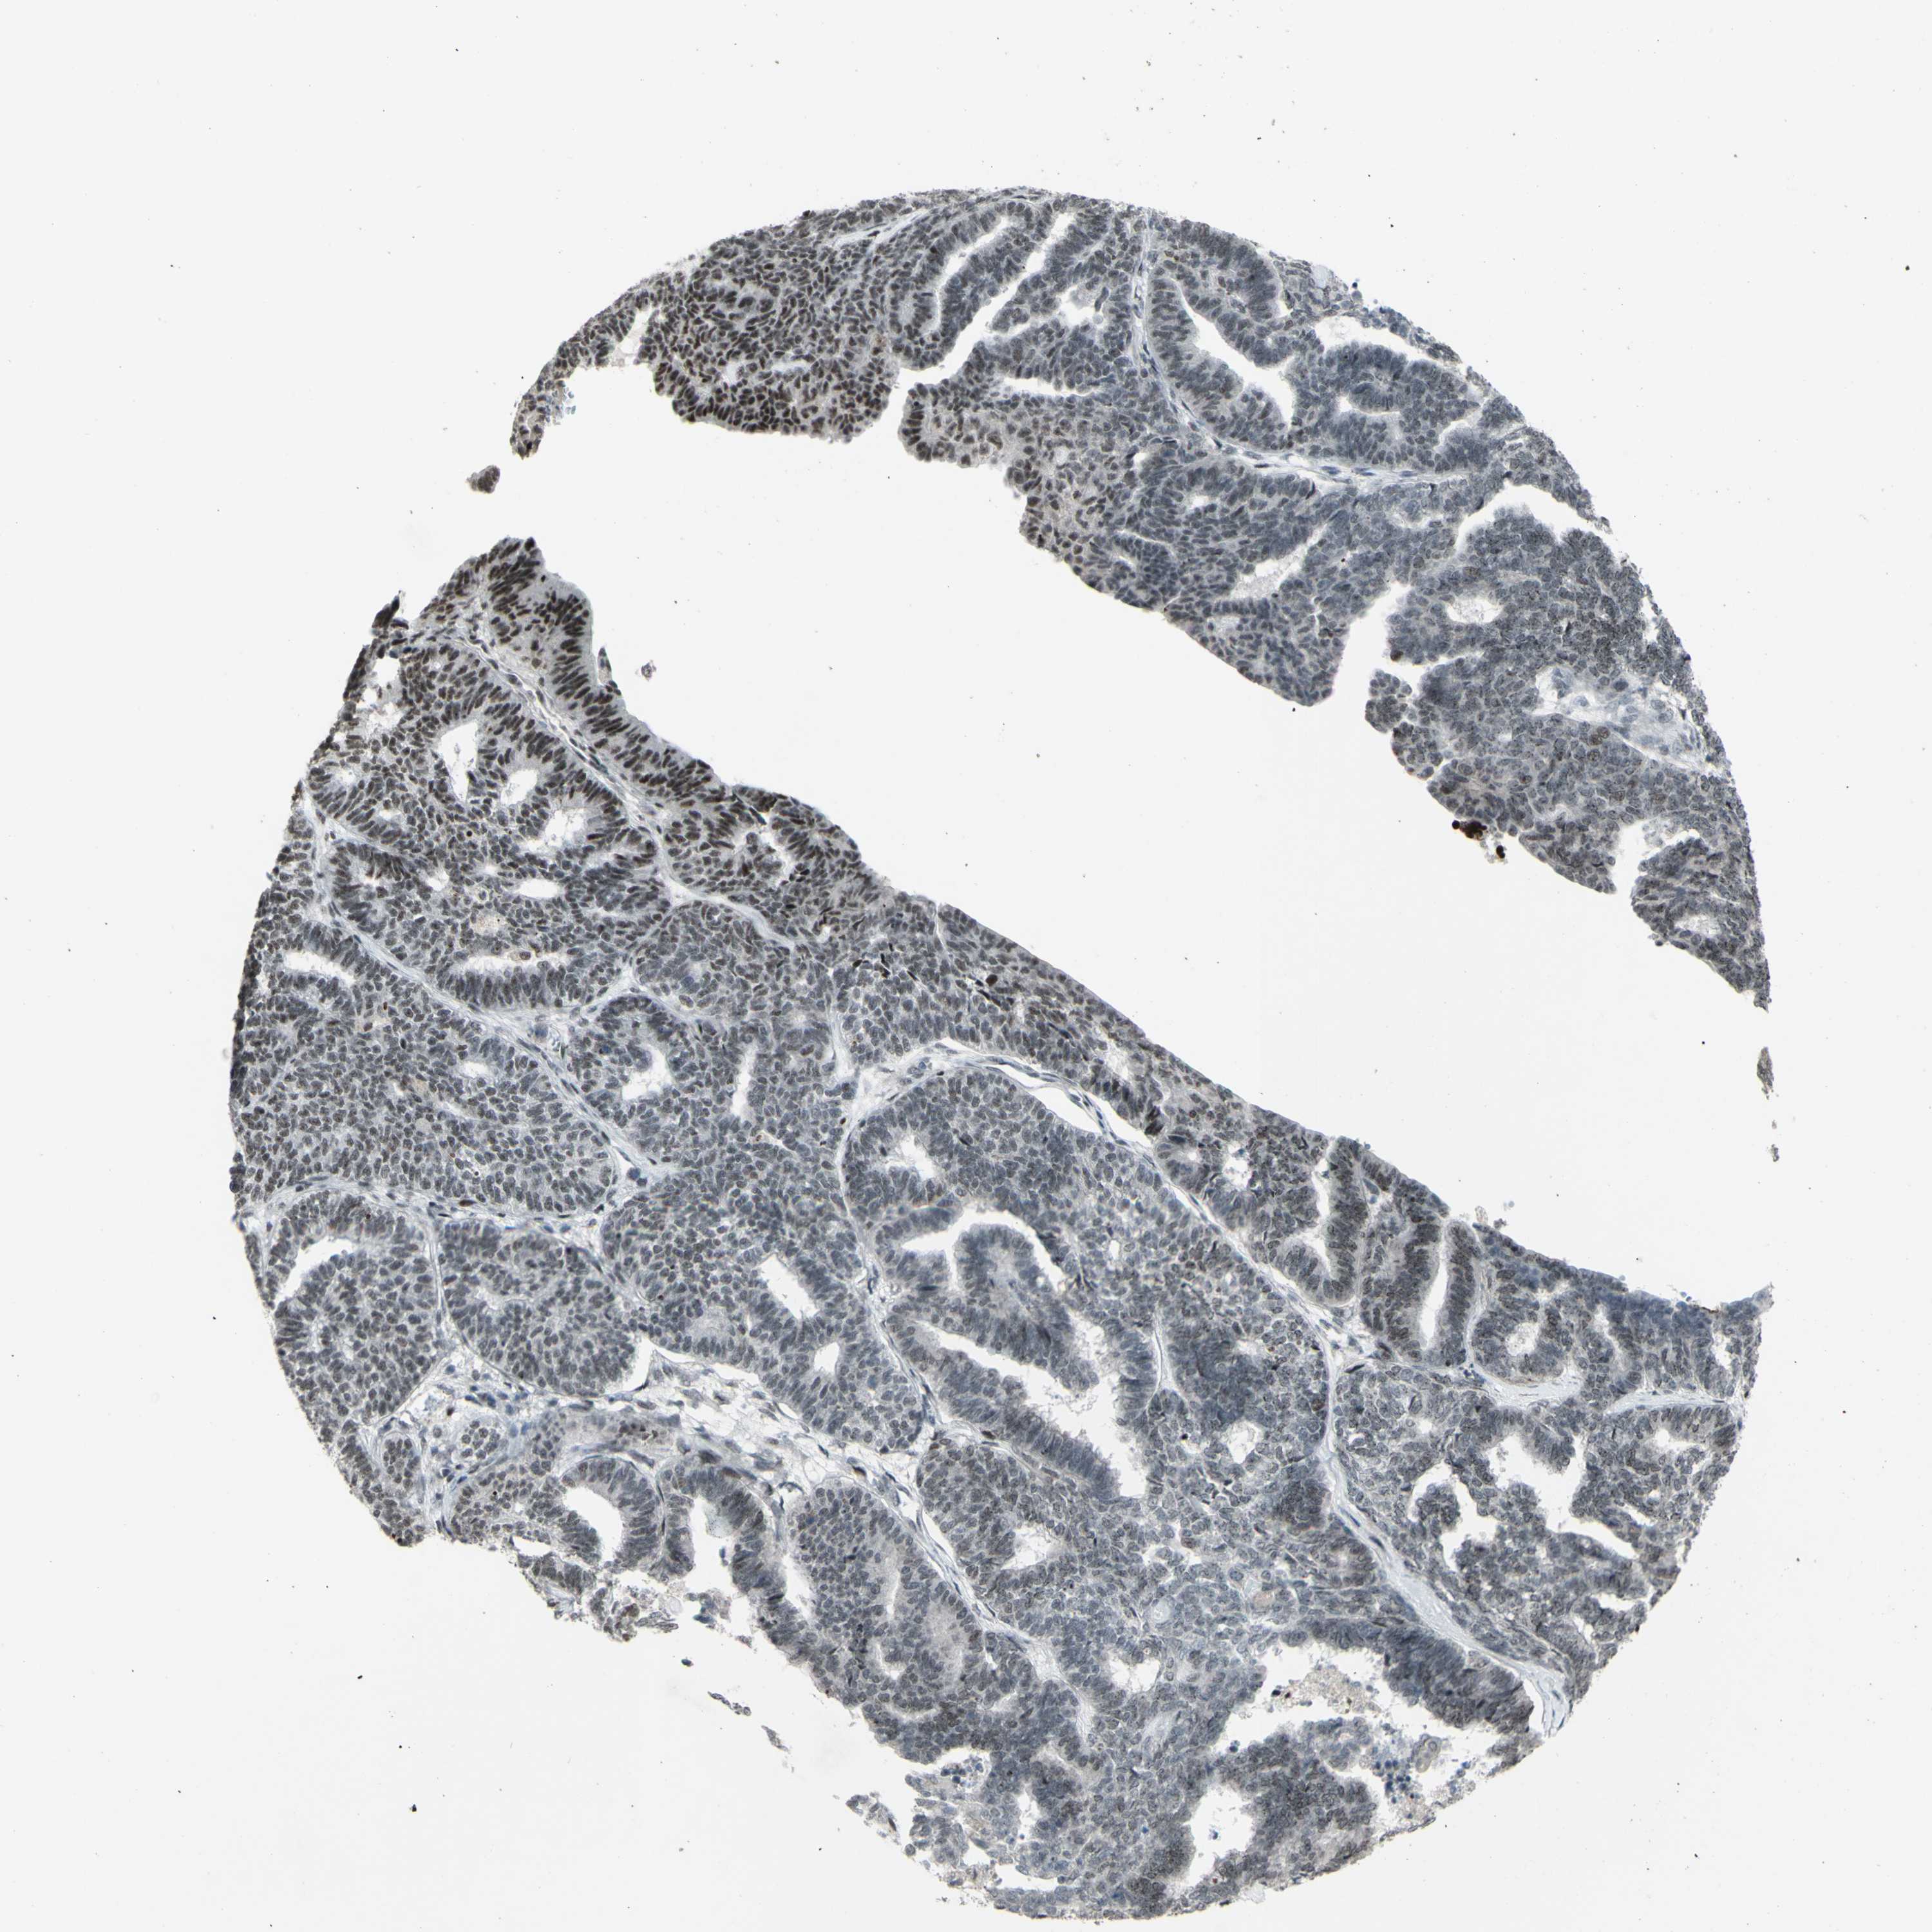

ENDOMETRIAL CANCER - Protein expressioni

A mouse-over function shows sample information and annotation data. Click on an image to view it in a full screen mode. Samples can be filtered based on level of antibody staining by selecting one or several of the following categories: high, medium, low and not detected. The assay and annotation is described here.

Note that samples used for immunohistochemistry by the Human Protein Atlas do not correspond to samples in the TCGA dataset.

Antibody stainingi

Antibody staining in the annotated cell types in the current human tissue is reported as not detected, low, medium, or high, based on conventional immunohistochemistry profiling in selected tissues. This score is based on the combination of the staining intensity and fraction of stained cells.

Each image is clickable and will lead to virtual microscopy that enables deeper exploration of all samples and also displays staining intensity scores, fraction scores and subcellular localization as well as patient and tissue information for each sample.

Antibody HPA036382

Antibody CAB012416

Staining

High

Medium

Low

Not detected

Intensity

Strong

Moderate

Weak

Negative

Quantity

>75%

75%-25%

<25%

None

Location

Nuclear

Cytoplasmic/membranous

Cytoplasmic/membranous,nuclear

Adenocarcinoma, NOS